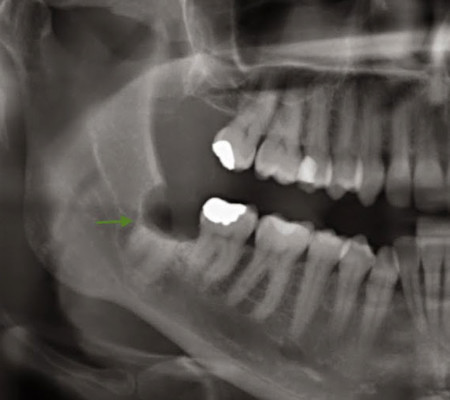

Billy Taylor estava com forte dor de dente. Ele ligou para consultórios odontológicos de emergência, mas nenhum deles estava atendendo por causa da quarentena pelo coronavírus. O morador de Axminster (Inglaterra), de 33 anos, chegou a ligar para hospitais. Mas a resposta era a mesma: só poderiam atendê-lo se estivesse com dificuldade para respirar. As informações são do Extra.

O jeito foi resolver sozinho. Com a ajuda de uma ferramenta de trabalho, o inglês arrancou o próprio dente, depois de muito esforço. Como "anestésico", ele bebeu algumas doses de uísque, contou reportagem do "Metro".